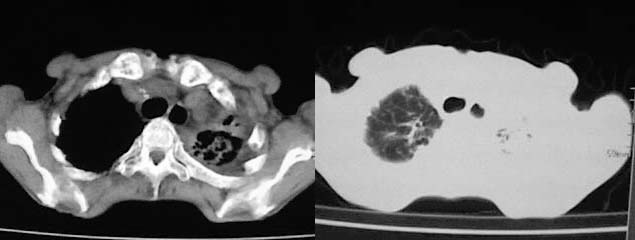

以下是引用zjzjr在2008-5-2 14:39:00的发言:[br]支持双侧继发型肺结核,左侧胸膜肥厚,慢性支气管炎伴间质纤维化.

以下是引用有风的日子在2008-5-2 12:13:00的发言:[br][emb10][br][br]肺ca?有病理支持吗?[br][br]我看更象是肺tb并支扩、间质性肺炎。最好拿个病理结果来,不然这点影像资料诊断肺ca是难以服人的![br][br]至于主动脉瘤的诊断问题,国外认为≥4.0cm就可诊断了,国内对此诊断标准更为严格。患者升主动脉明显增粗,即>4cm。你诊断个升主动脉扩张并不为过!